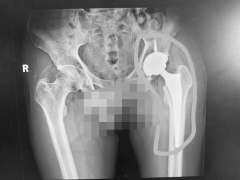

“之前的骨科医生应该是受到了王女士的诱导,因为她见到医生就说自己是腰脱,导致医生忽视了其他骨科疾病的诊断。腿变短了,可能是股骨头出了问题。”蔡振存表示。通过股骨头部位的影像检测,王女士被确诊为股骨头坏死。通过股骨头置换手术,王女士的病得到了彻底解决。